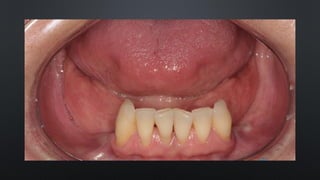

• OVERJET OU SOBRESALIÊNCIA

RELAÇÃO ENTRE ARCOS

TRESPASSE HORIZONTAL

• REFERE-SE AO DISTANCIAMENTO ENTRE OS INCISIVOS SUPERIORES E INFERIORES

• NORMALMENTE 2MM

• OVERJET OUSOBRESALIÊNCIA RELAÇÃO ENTRE ARCOS TRESPASSE HORIZONTAL • REFERE-SE AO DISTANCIAMENTO ENTRE OS INCISIVOS SUPERIORES E INFERIORES • NORMALMENTE 2MM